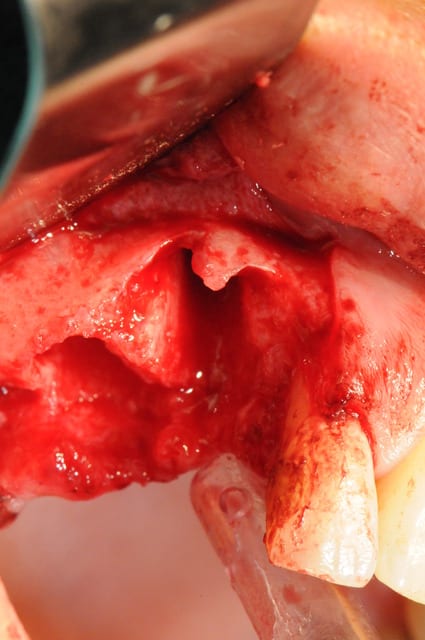

Patiente présente une perte alvéolaire de la table externe suite à fracture radiculaire.

J'ai réalisé un lambeau tracté coronairement mais je pense que certains auraient peut-être réalisé un lambeau conjonctif palatin.

Il manque juste une photo de la membrane biogide que je ne retrouve pas.

la pose est de jeudi dernier mon apn est en panne, photo avec le portable, desolé pour le sang mais quand cela saigne il n'y a pas d'échec